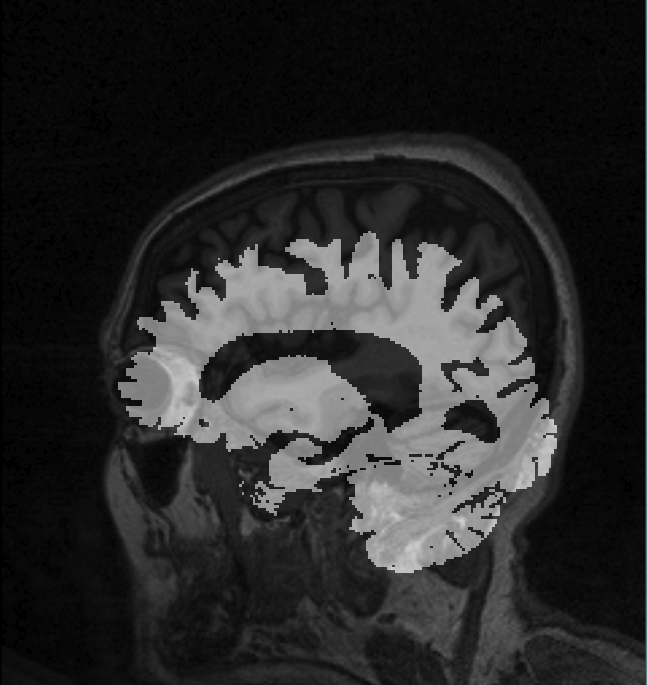

The aim is to display a brain segmentation overlapped on a T1 MRI image (both Nifti) using AMI. The problem is that the brain segmentation appears shifted from the T1. However, when I load these images with Papaya web viewer, FreeView or MRView, everything is properly registered.

Image properly registered, loaded with the Papaya web viewer.